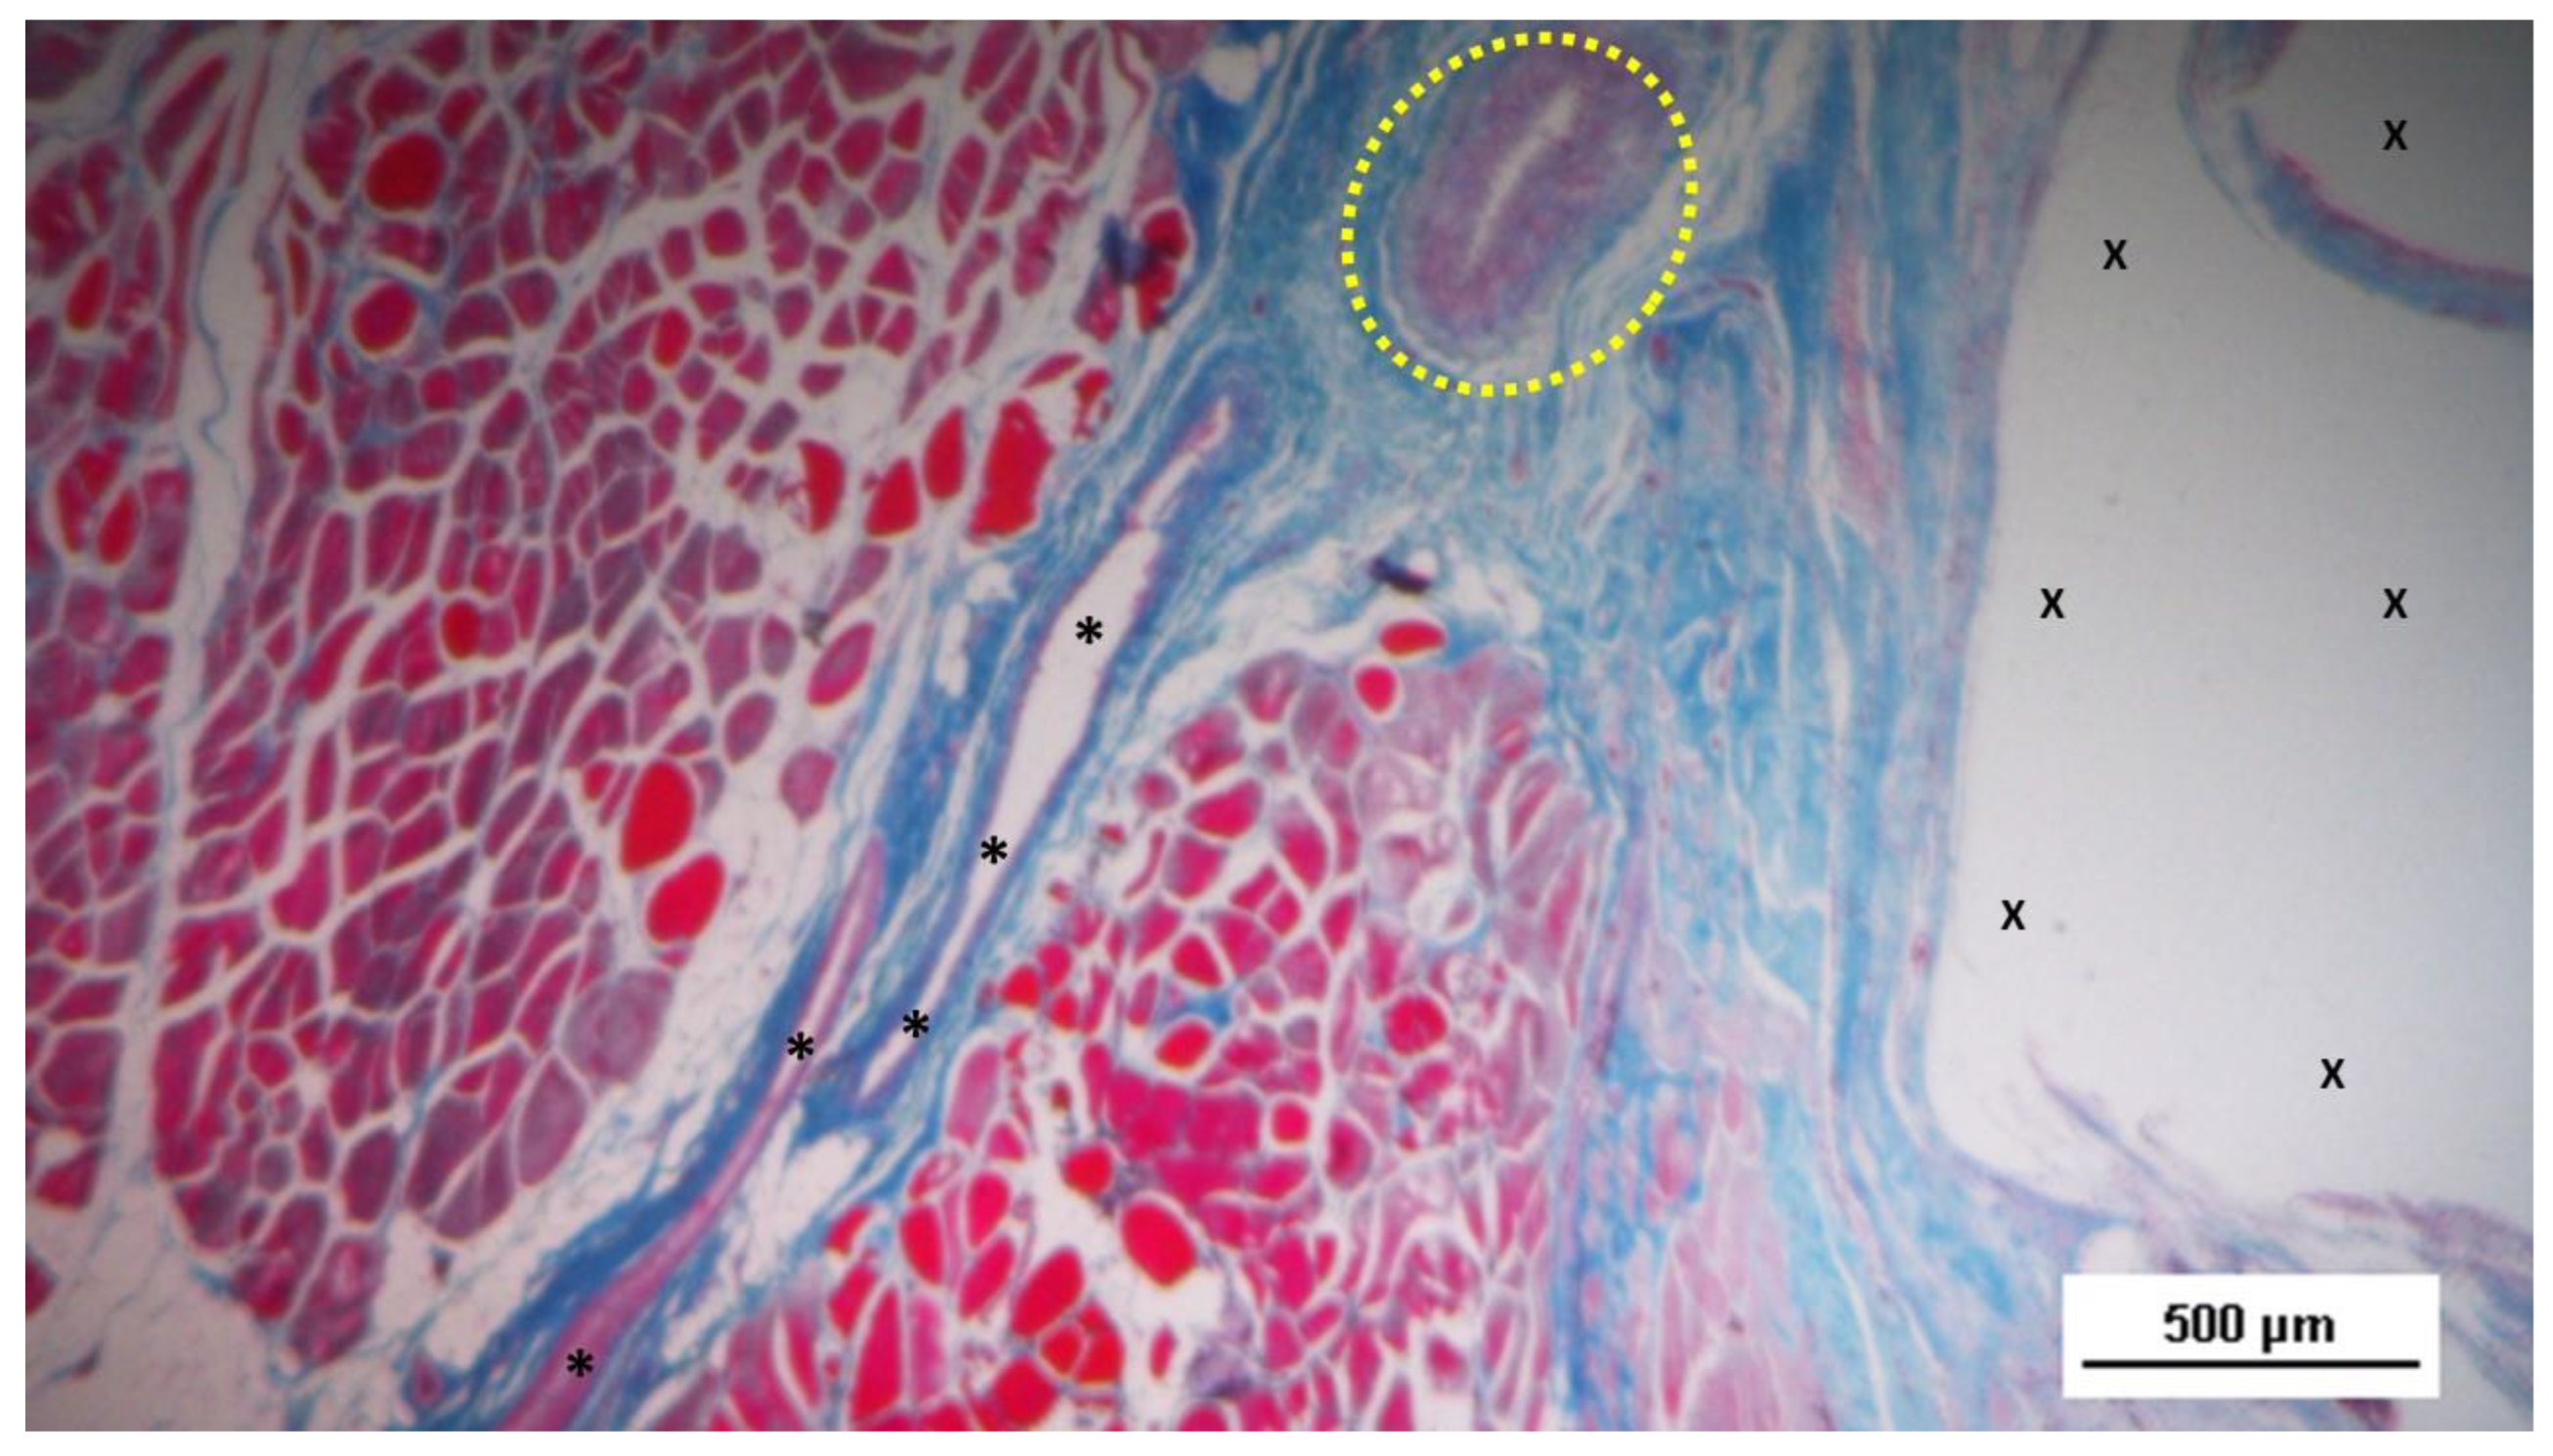

S&S fabric (X). - AM 50X

Figure 6.

Biopsy specimen excised 5 weeks post-op: in a surround of well-organized connective tissue, numerous clusters of muscle elements, together with large areas of structured muscle fascicles, are evident adjacent to the 3D scaffold of the device (X). AM 50X.

Actually, the typical features of the early phase of muscle development, characterized by vesiculated nuclei, prominent nucleoli and moderate basophilia, were markedly evidenced in the newly ingrown tissue.

The development of muscle elements in biopsy samples taken from the 3D scaffold of the S&S device 3 to 4 months after placement (mid-term) showed a noticeable increase in both quantity and quality. At this stage, a greater number of muscle element clusters, along with extensive areas of muscle bundles, were observed adjacent to the device fabric and interspersed within well-organized connective tissue (